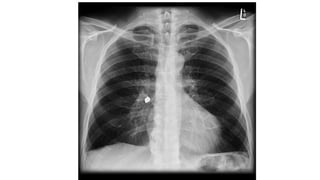

The document presents a chest X-ray examination summary by Ninian Peckitt, detailing various respiratory conditions including tracheal deviation, pleural effusions, and lung collapses. Findings suggest thoracic trauma and hyperinflation in the lungs. Additionally, it includes links to medical products and their pricing.